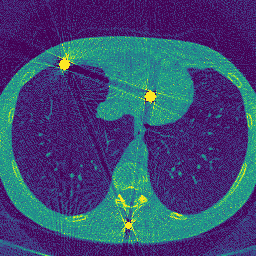

Real Scenes

We benchmark against baseline methods (FDK, LIMAR) and NeRF-based MAR approaches (Park et al., Polyner) across synthetic and real scenes. Our method consistently achieves superior artifact reduction while preserving fine structural details.